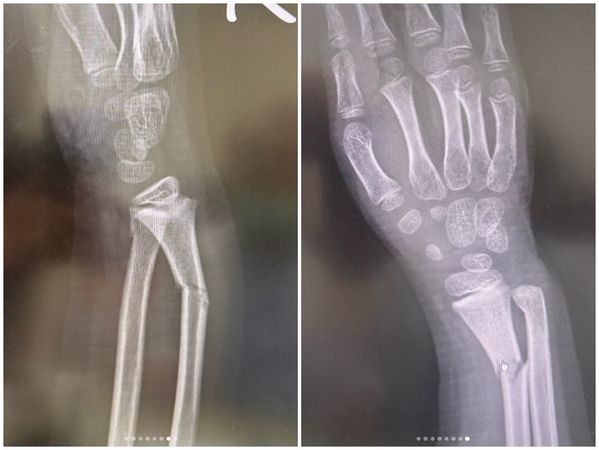

▲白家綺曝光兒子的X光照。(圖/翻攝自Instagram/sabrinapai0420)